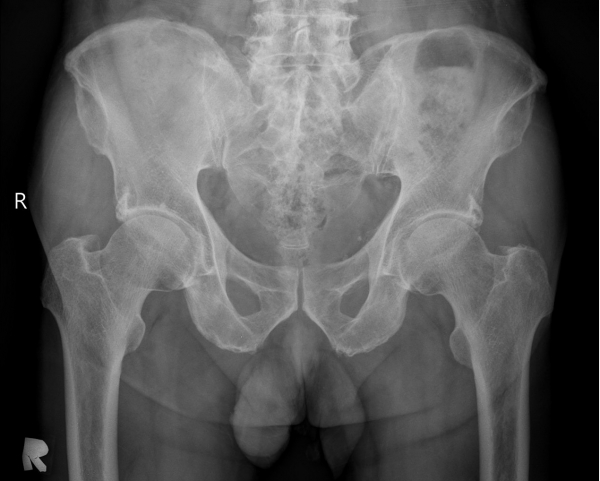

[¾ûµ¢ÀÌ] °í°üÀý Ãæµ¹ÁõÈıº¿¡ÀÇÇÑ È°¾×¸·¿° ÁÖ»çÄ¡·á